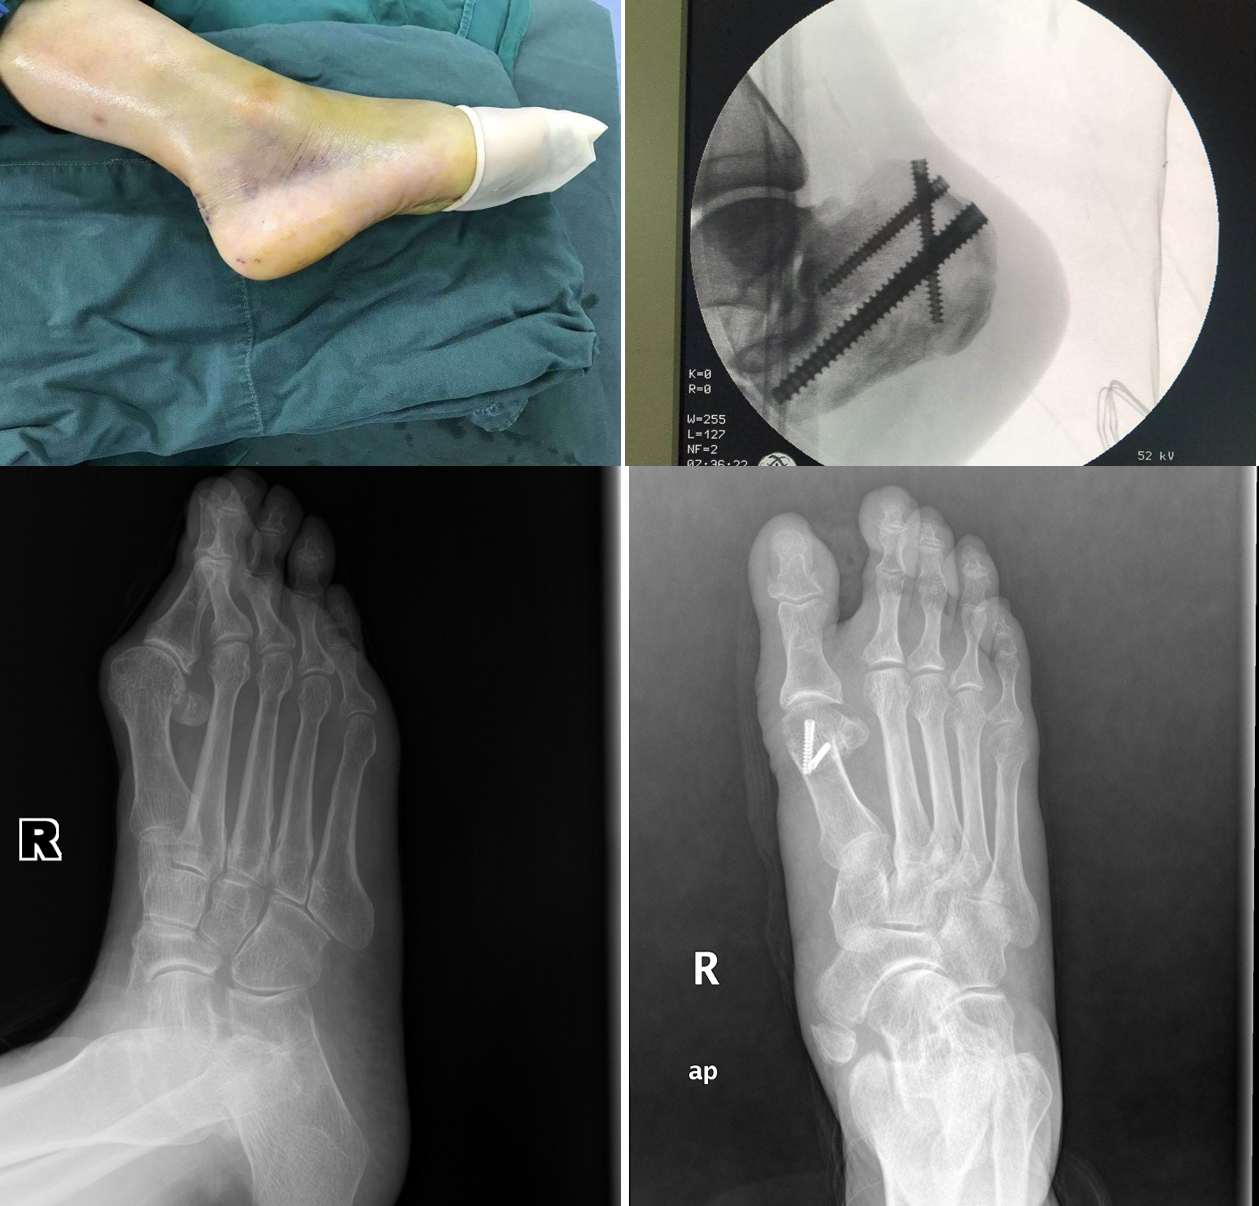

两年来共收治住院患者1200余人次,手术900余台次,积极利用医院提供的平台,为广大患者带来福音。在治疗各种足踝损伤及足踝畸形方面取得了不错的成绩。刘峰主任首创的撬拨复位全螺纹螺钉固定微创治疗跟骨骨折具有创伤小,恢复快,并发症少,住院时间短,费用低廉等优点,得到省内同行的好评,两年来共使用此手术方式治疗跟骨骨折百余例,并经常下到基层进行推广指导。本科室有着先进的足踝畸形矫正技术,两年来治疗了50余例足踝畸形,治疗经验丰富,主要有踇外翻的个性化中西医结合矫正治疗,扁平足、复杂马蹄高弓内翻足、踝关节炎等各种畸形的手术矫正治疗,创伤后畸形及功能重建治疗等。